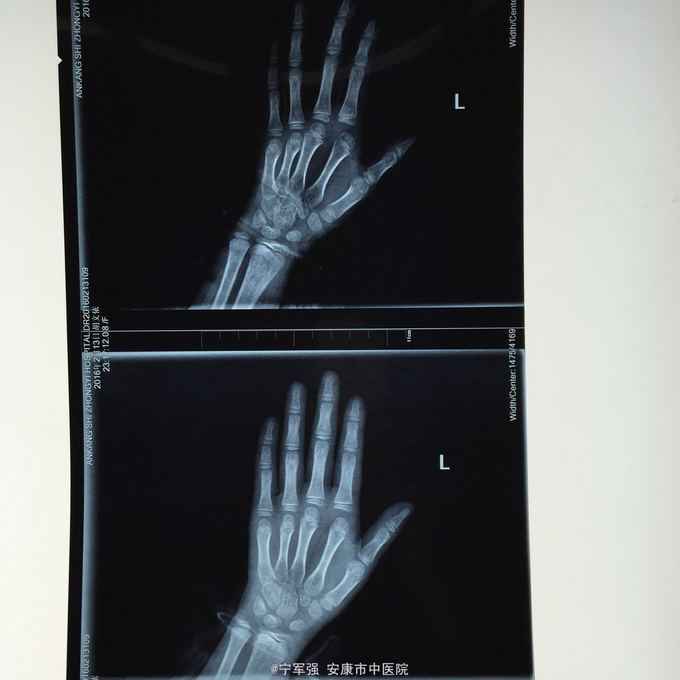

患者8岁,女 扭伤致左手食指肿痛活动受限2小时

患者一般情况良好,左手第二掌指关节处肿胀,弹性固定于伸直位,活动受限,压痛明显,循环尚可

诊断:左手第二掌指关节脱位 处理,予以手法复位失败!考虑关节囊坎顿,阻止复位 予以局麻小切口探查证实,复位脱位,修补关节囊

指骨夹板固定,复查x线显示复位良好 随诊